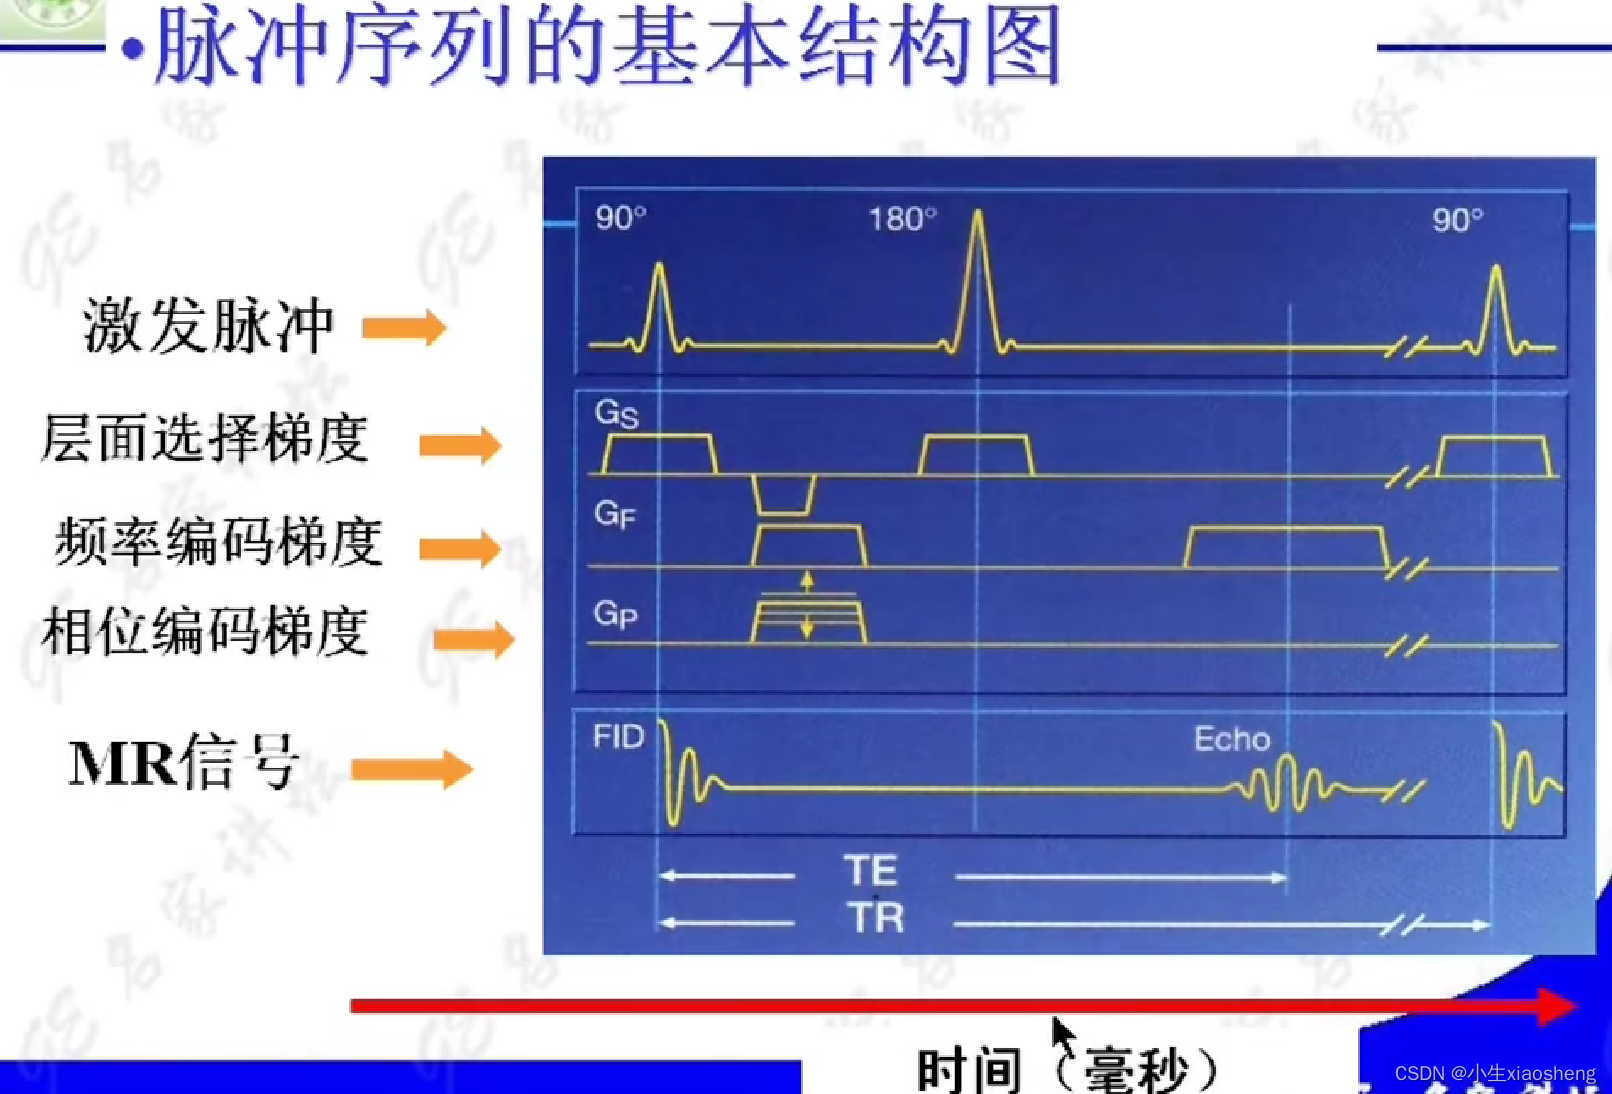

TR代表重复时间(repetition time),是指脉冲序列执行所需的时间

TE代表回波时间(echo time),是指产生宏观横向磁化矢量的脉冲中点到回波中点的时间间隔

相位编码梯度和频率编码梯度/读出梯度:主要功能就是在脉冲消失之后采集数据,能横向量编码很快衰减。

90度和180度共同来组成一条K空间线。

因为这里有很多的180度,所以一次能填充很多K空间线。两个90度之间的时间还是叫做TR,180度的个数叫做ETL,90度到中间个数的180度叫做有效TE,两个180度之间的叫做ES。